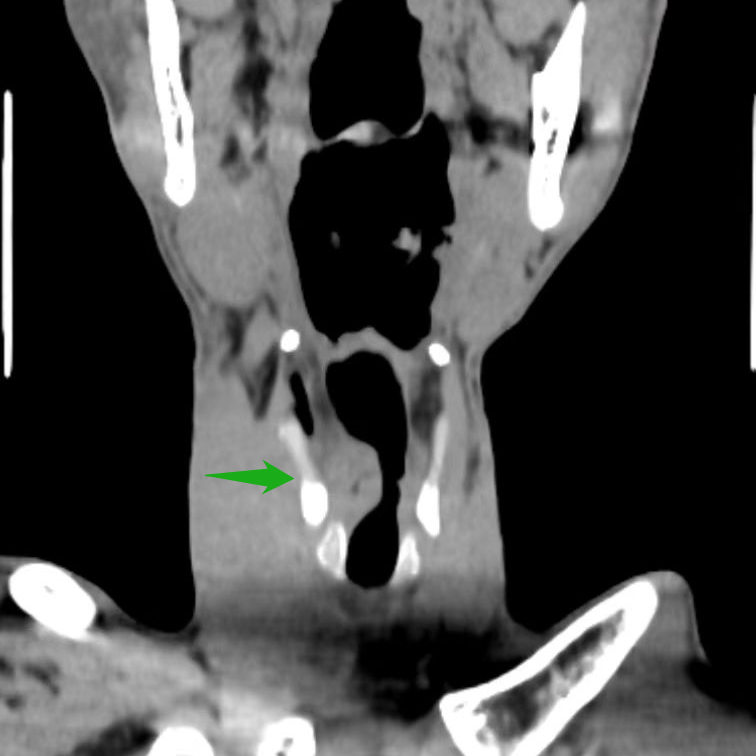

医生考虑喉新生物为恶性肿瘤,已经到了中晚期,建议先活检,再全喉切除。但张大叔平日里喜欢与朋友畅谈,不肯切全喉,家里的亲戚轮番来劝。耳鼻咽喉头颈外科刘蓉蓉主任、姬长友教授接诊后,立刻完善颈部 CT,显示 1. 右侧室带及声带增厚伴软组织结节形成,考虑新生物,建议病理组织学检查 2. 颈部少许小淋巴结。

取右侧声带病变组织活检,证实了喉癌的判断。考虑到喉癌范围极大,右侧声带已经固定,建议张大叔全喉切除。但其仍「意志坚定」,坚决不切全喉。刘蓉蓉主任、姬长友教授详细研究,制定了把右喉体及右侧甲状软骨板「连锅端」,保留左侧喉组织的方案,既可以彻底解决问题,又照顾到张大叔关于保留喉功能的顾虑。